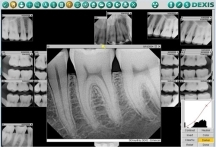

What about x-rays used in dental work during pregnancy?

Routine x-rays, usually taken during annual exams, can usually be postponed until after the birth. X-rays are necessary to perform many dental procedures, especially emergencies. According to the American College of Radiology, no single diagnostic x-ray has a radiation dose significant enough to cause adverse effects in a developing embryo or fetus.